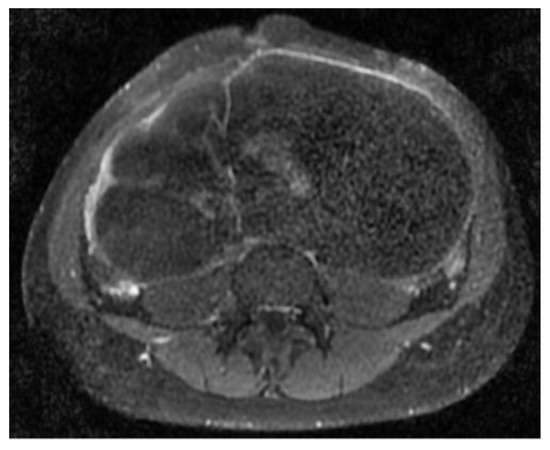

The abdomino-pelvic US showed a thin-walled, multilocular cystic mass occupying almost the entire abdomen and pelvis, with transonic content and multiple septa, some of them thick. None of the ovaries were visualized, and there was no free peritoneal fluid. Because the cyst origin could not be specified, we requested an abdomino-pelvic MRI, which showed a 115/224/350 mm cystic tumor originating in the right ovary that waswell-defined by a regular wall, multiloculated, had liquid content with some areas of high signal intensity in T1, and presented moderate mural and septal enhancement after gadolinium injection; the suggested diagnosis was ovarian cystadenoma (Figure 2 and Figure 3).

Figure 2. Coronal STIR sequence shows a well-defined voluminous, multiloculated, multiseptate cystic mass occupying the pelvis and the large peritoneal cavity.